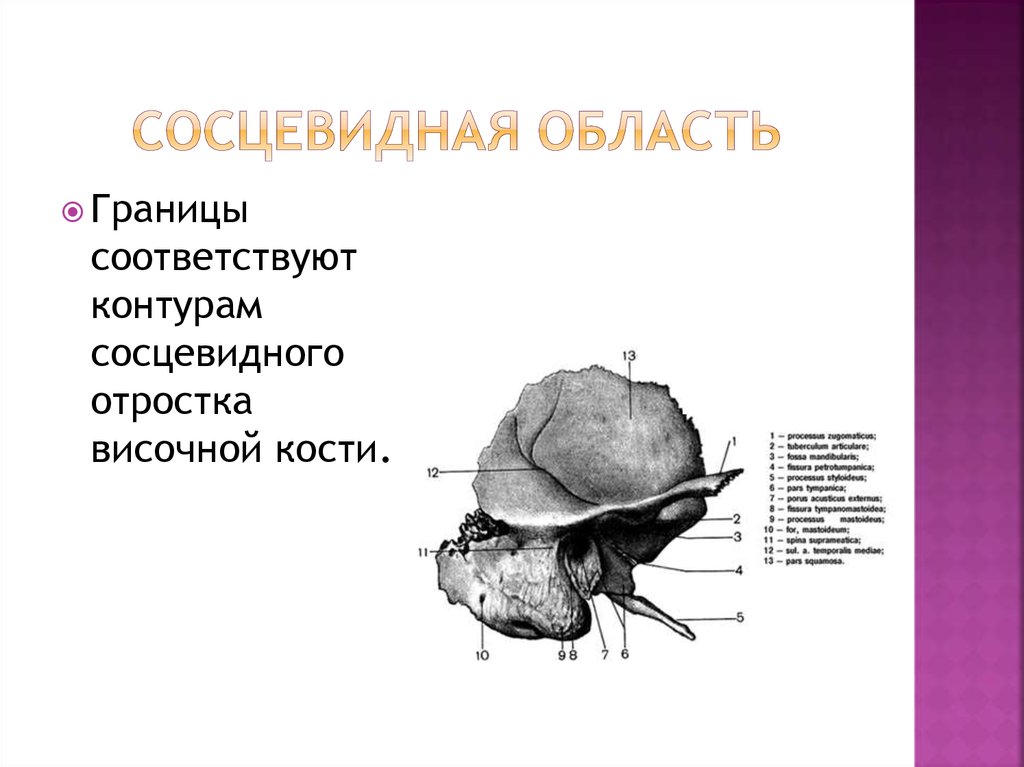

Анатомия сосцевидного отростка